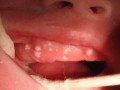

• 小疙瘩/红斑: 外阴皮肤可能出现红肿、红斑,上面附着有白色膜状物,去除后可见糜烂面,有时也会出现小米粒大小的小疙瘩或丘疹。

• 菜花状或鸡冠状赘生物: 肉眼可见的小疙瘩,可能单个或多个,呈灰白色、粉红色或污灰色。